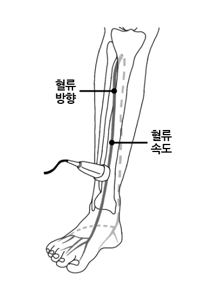

- 도플러 초음파 검사 (Duplex ultrasound)

- 하지정맥류 진단에 가장 중요하고 기본이 되는 비침습 검사입니다.

- 혈관 초음파로 혈관 구조를 확인하고 도플러를 통해 혈액의 흐름 방향, 속도, 역류 여부 및 역류 시간을 측정합니다.

- 이 검사를 통해 정맥 내 판막 손상 부위에서 혈액이 역류하는 정도를 평가하고, 정맥류의 원인이 되는 혈관을 정확히 찾아낼 수 있습니다.

- 검사 방법은 일반 초음파 검사와 유사하며, 숙련된 검사자가 시행해야 정확도가 높습니다.